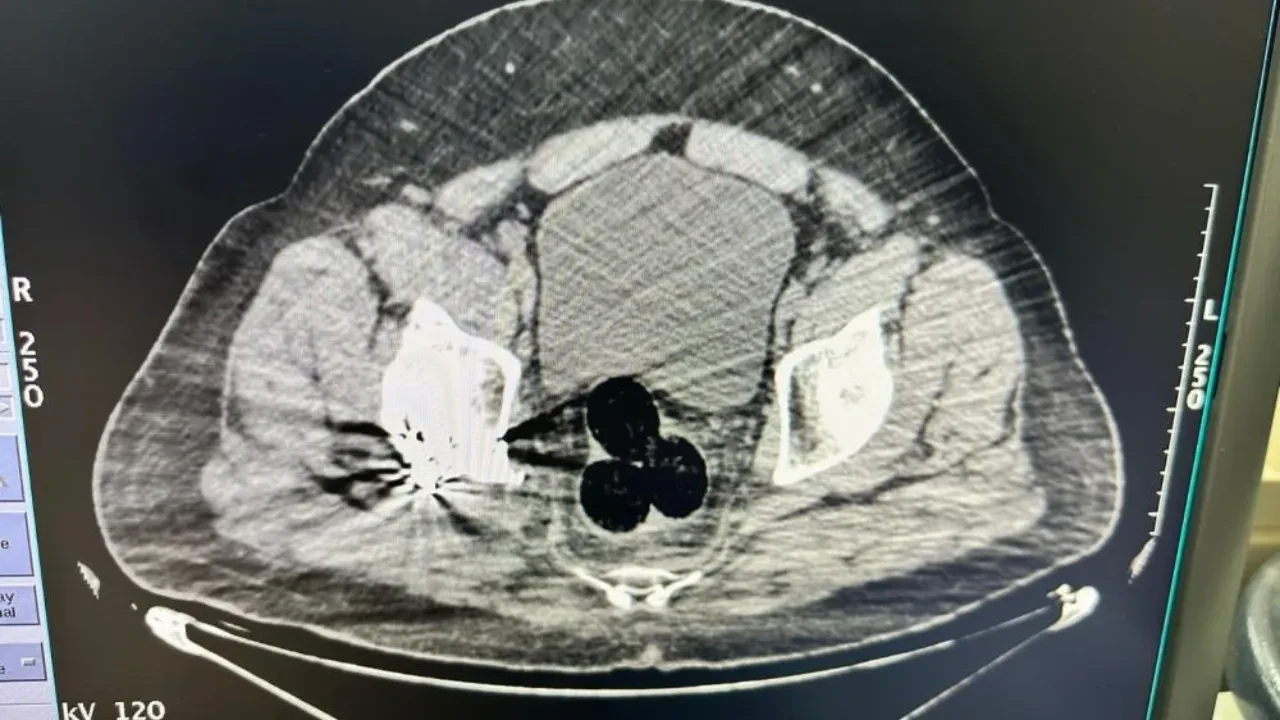

Gözaltına alınan şahıs hastaneye götürüldü. Hastanede yapılan görüntülemede şüphelinin makat bölgesinde üç parça halinde yabancı cisim tespit edildi. Cerrahi müdahale ile çıkarılan paketlerde toplam 130 gram metamfetamin ele geçirildi, şüpheli gözaltına alındı.